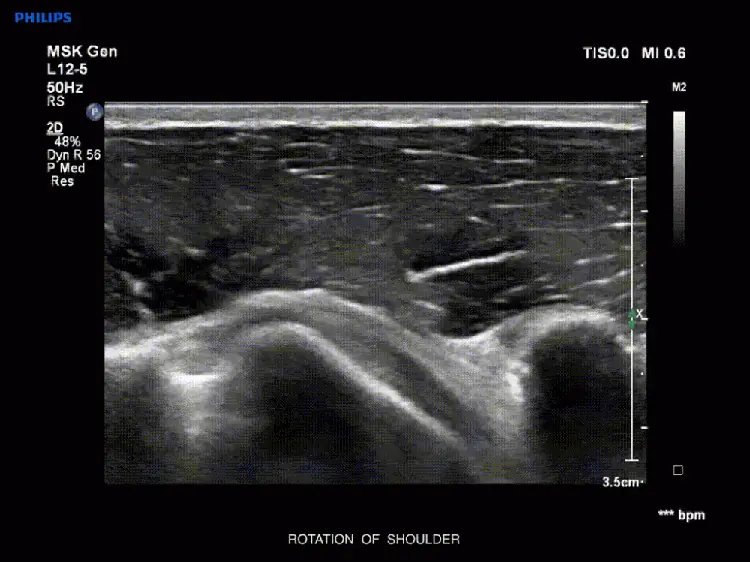

Duchenne J, Martinez M, Rothmann C, et al. Premier niveau de compĂ©tence pour lâĂ©chographie clinique en mĂ©decine dâurgence (ECMU 1). Recommandations de la SociĂ©tĂ© française de mĂ©decine dâurgence par consensus formalisĂ©. Ann Fr Med Urgence. 2016;6(4):284-295.